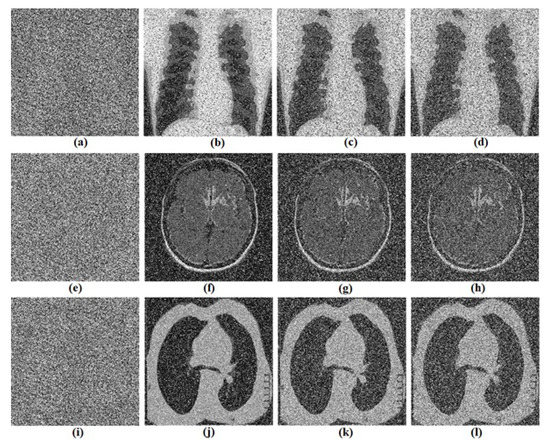

5. Biomedical Images Encryption Based on RNG Obtained from the Oscillator

5.1. Proposed Biomedical Images Encryption Algorithm

5.2. Computational Results

5.3.2. Key Sensitivity Analysis